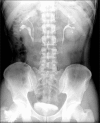

We present two cases of symptomatic lower pole moiety ureteropelvic junction obstruction (UPJO) in a partially duplicated collecting system that were successfully treated with minimally invasive endourologic procedures. In the first case, we performed retrograde endopyelotomy with the Acucise(R) ureteral cutting balloon device, and in the latter case, we performed percutaneous nephrolithotomy and antegrade endopyelotomy because of the presence of multiple renal stones. Subsequent intravenous pyelography confirmed marked resolution of the obstruction, and both patients remained asymptomatic during 1 year of follow-up.